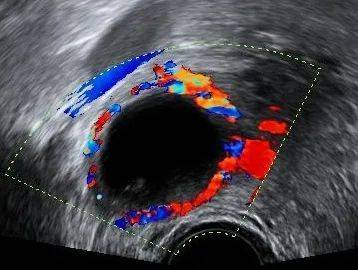

正如上文所说,由于B超下发现的毕竟只是一个影像,所以很多时候并不能判断囊肿的性质,还需要进一步随访 或检查才能判断。国际卵巢肿瘤分析组织(IOTA)将卵巢肿瘤的超声描述方法标准化,在以下识别卵巢肿瘤良恶性 的10个简单特征中,若卵巢肿瘤含有至少一个恶性肿瘤特征(M特征)而没有良性肿瘤特征(B 特征),则卵巢肿 瘤被分类为恶性肿瘤。

在超声检查的同时,还可以检查肿瘤标志物。当对囊肿的性质做了初步判断后,我们便可以对号入座看看如何 处理。若提示有癌变风险,一般建议手术治疗。而良性囊肿处理方法则各不相同。